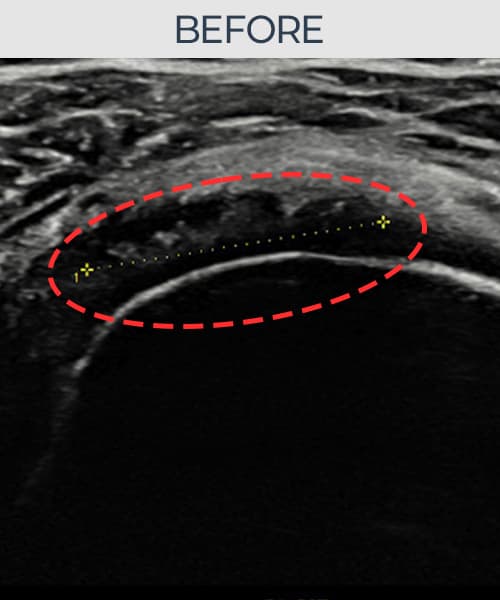

실제 환자의 시술 전후 초음파 영상입니다.

수술 없이 이뤄낸 회복을 직접 확인하세요.

모든 초음파 영상은 실제 환자의 동의를 받아 게시하였습니다. 개인차가 있으며 동일한 결과를 보장하지 않습니다.